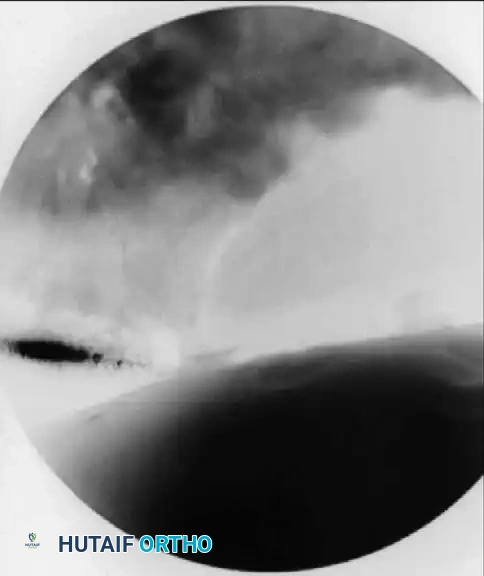

- Distraction: Apply traction to the operative extremity. Confirm adequate distraction of the joint space fluoroscopically before proceeding with portal placement.

- Initial Access: Establish the anterolateral portal first using a 6-inch, 17-gauge or 18-gauge spinal needle under continuous fluoroscopic guidance.

- Capsular Penetration: If excessive resistance is met during needle placement, redirect it under fluoroscopic control, aiming slightly more parallel to the femoral head and away from the cartilaginous edge of the acetabulum to prevent iatrogenic labral puncture.

- Venting the Joint: Distend the joint with 30 to 50 mL of sterile saline. A reverse flow of fluid signals successful entrance into the intra-articular space and breaks the vacuum seal, allowing the joint to distract fully.

- Cannula Insertion: Pass a flexible nitinol guidewire through the needle, withdraw the needle, and pass the cannulated obturator and sheath assembly over the wire. Never use excessive force, which could score the femoral head.

- Establishing Secondary Portals: Pass a spinal needle into the joint to create the anterior and posterolateral portals, directly observing the needle's entry with a 70-degree arthroscope from the anterolateral portal. Verify all placements with fluoroscopy.